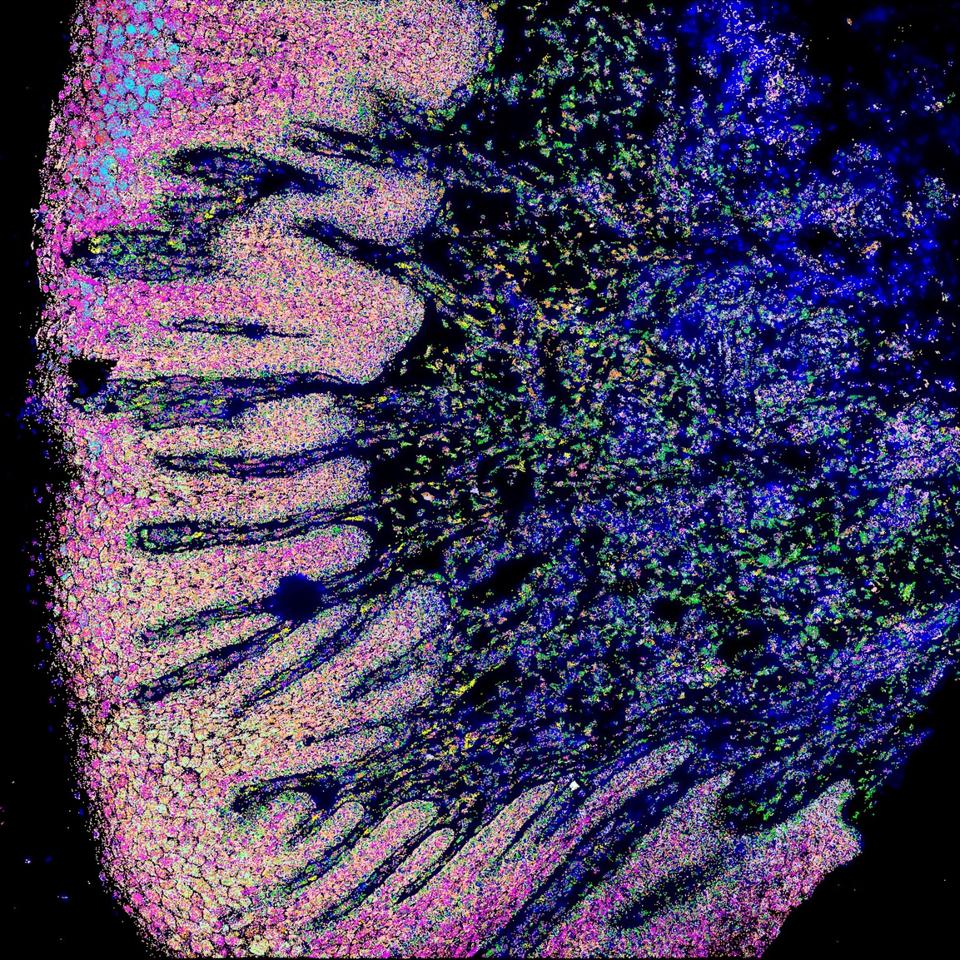

Researchers used Resolve’s technology to create this image of healthy and diseased gum tissue in a dental patient.

Founded in 2020 by Gammack, Axel Heinemann, 57 and Peer Schatz, 57, Resolve Biosciences aims to close that gap quickly with what it calls its “Molecular Cartography” technology. This enables researchers, Gammack says, to understand not only the genetic structure of, say, a tumor cell, but also a stronger understanding of what’s happening in that cell’s environment. “Scientists can now get a view of individual cells and their interactions within the tissue in the three dimensional space,” he says.

For its customers, which include the Novo Nordisk Foundation Center, the Stanford Medicine Department of Genetics and the European Spatial Biology Center, Resolve’s technology provides high-resolution images of gene expression at the subcellular level. For example, a recent experiment using Resolve’s technology was used to create an atlas of healthy and obese liver cells. Those results were published in the journal Cell.